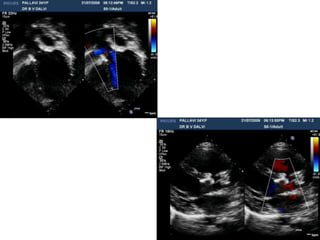

dications for VSD Closure

 Relevant shunt:

 Qp/Qs > 2 : 1 and LV volume overload

 Qp/Qs > 1.5 : 1* and

 PA pressure < 2/3 of systemic pressure and

PVR < 2/3 of systemic Vascular resistance

 Qp/Qs > 1.5 : 1 and

 LV systolic or diastolic failure

 History of endocarditis

*CCS Guidelines 2006, AHA Guidelines 2008 /ESC 2012

Indications for VSD closure

LV overload

Z-score of LVEDD > +2

Doppler gradients across the VSD to estimate RV pressure

RV pressure? Reversible PHT?

INDICATIONS FOR VSD

CLOSURE

QP:QS

Qp/Qs can be estimated by using 2D echo

and spectral Doppler measurements

Echocardiographic delineation of pmVSD

Echocardiographic delineation of various VSDs